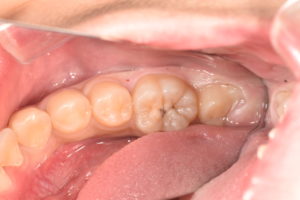

一定期間の経過観察の後、臨床症状に変化はなかったため、ダイレクトボンディングにより歯冠部修復を行った。

MTAセメントは高い抗菌性や封鎖性のある材料で今回のようにラバーダムと併用することで、従来であれば取り除かなければならない歯髄も保存することができます。また、ダイレクトボンディングやセラミックによりピッタリ隙間なく封鎖することでその後の再感染を予防することが可能となってきます。